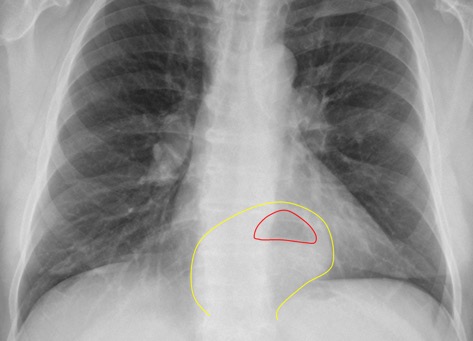

Look for gastric air bubble located in LUQ below the left hemidiaphragm and cardiac silhouette.

Hiatal hernias are very common. Usually seen as a rounded density at the midline behind the heart.

Sometimes an air-fluid level may be seen.

Diaphragmatic Hernia